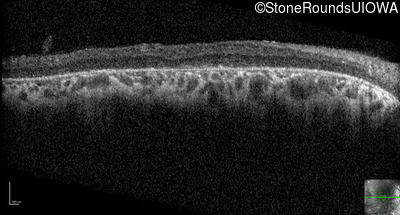

Optical Coherence Tomography - Right - 20/63 +1

Exemplar / OCT Stack